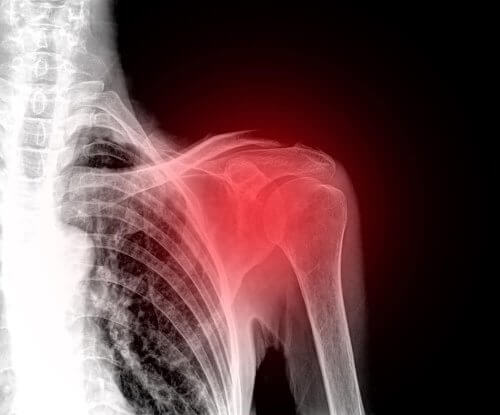

تمزق الكفة المدورة من الإصابات الشائعة بين البالغين والتي تصيب الكتفين. في الواقع، هذه الحالة هي أحد الأسباب الرئيسية لظهور آلام الكتف.

الكفة المدورة هي مجموعة من العضلات والأوتار التي تثبت عظام الكتف. وهي المسؤولة عن الحفاظ على استقرار المفصل والسماح له بتنفيذ جميع الحركات الممكنة بشكل طبيعي.

وللأسف، الكتف من أجزاء الجسم سهلة الضمور، وهو ما يؤدي عادةً إلى عدم الراحة. والإصابة في هذه المنطقة يمكن أن تكون مؤلمة ومعطلة جدًا. لذلك، نرغب اليوم في شرح كل ما تحتاج إلى معرفته بشأن حالة تمزق الكفة المدورة.